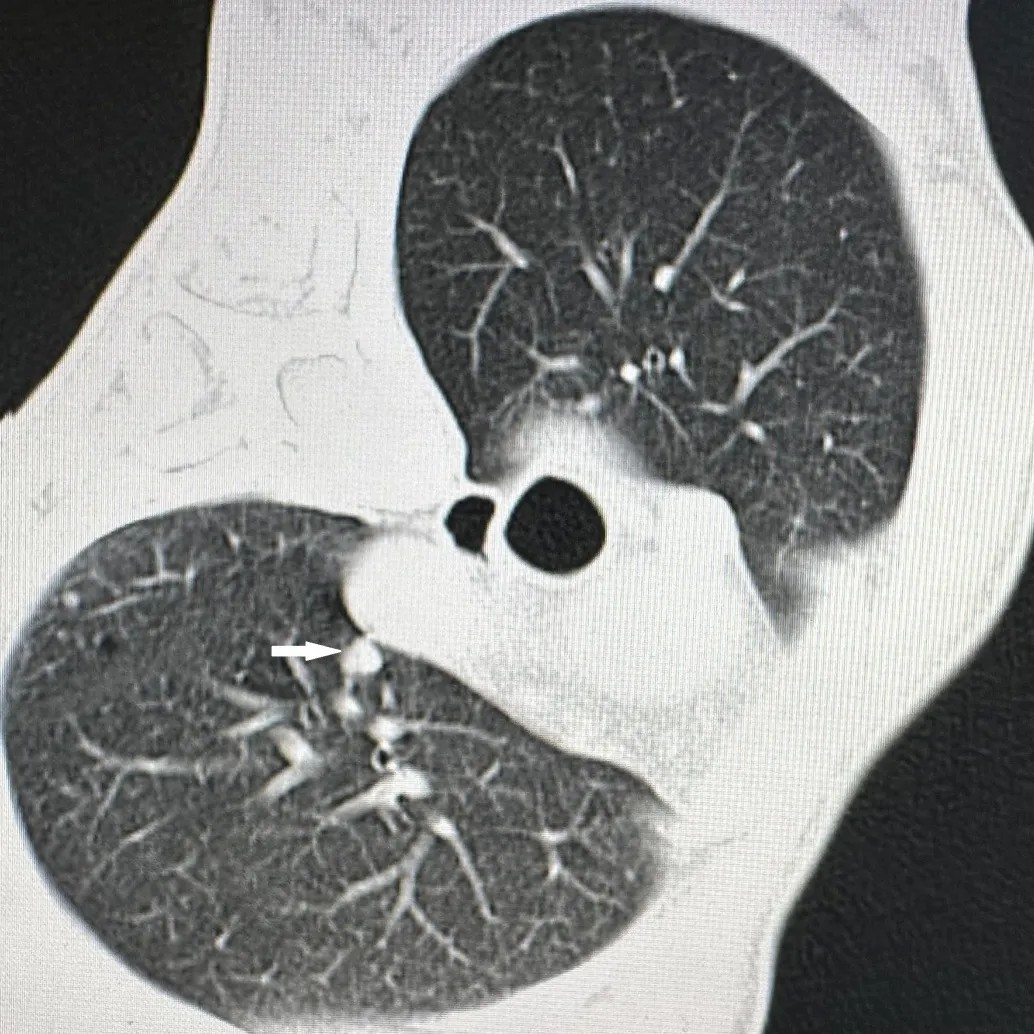

胸部CT显示肺上病灶一个位于肺上叶,因病灶位置较高,肋间隙较窄,比邻肩胛骨,给穿刺造成明显困难;另一个病灶紧邻主肺动脉,穿刺出血风险极高。7月25日,李建军主任经过仔细读片,认真分析,选择了最佳的穿刺路径,通过CT引导,在次旺晋美医师辅助,扎西次仁和德吉卓嘎护士配合下,一次手术对两个病灶进行了精准消融,术后CT扫描显示病灶完全坏死,未出现气胸等并发症,患者安返病房。

主肺动脉旁病灶(白色箭头)